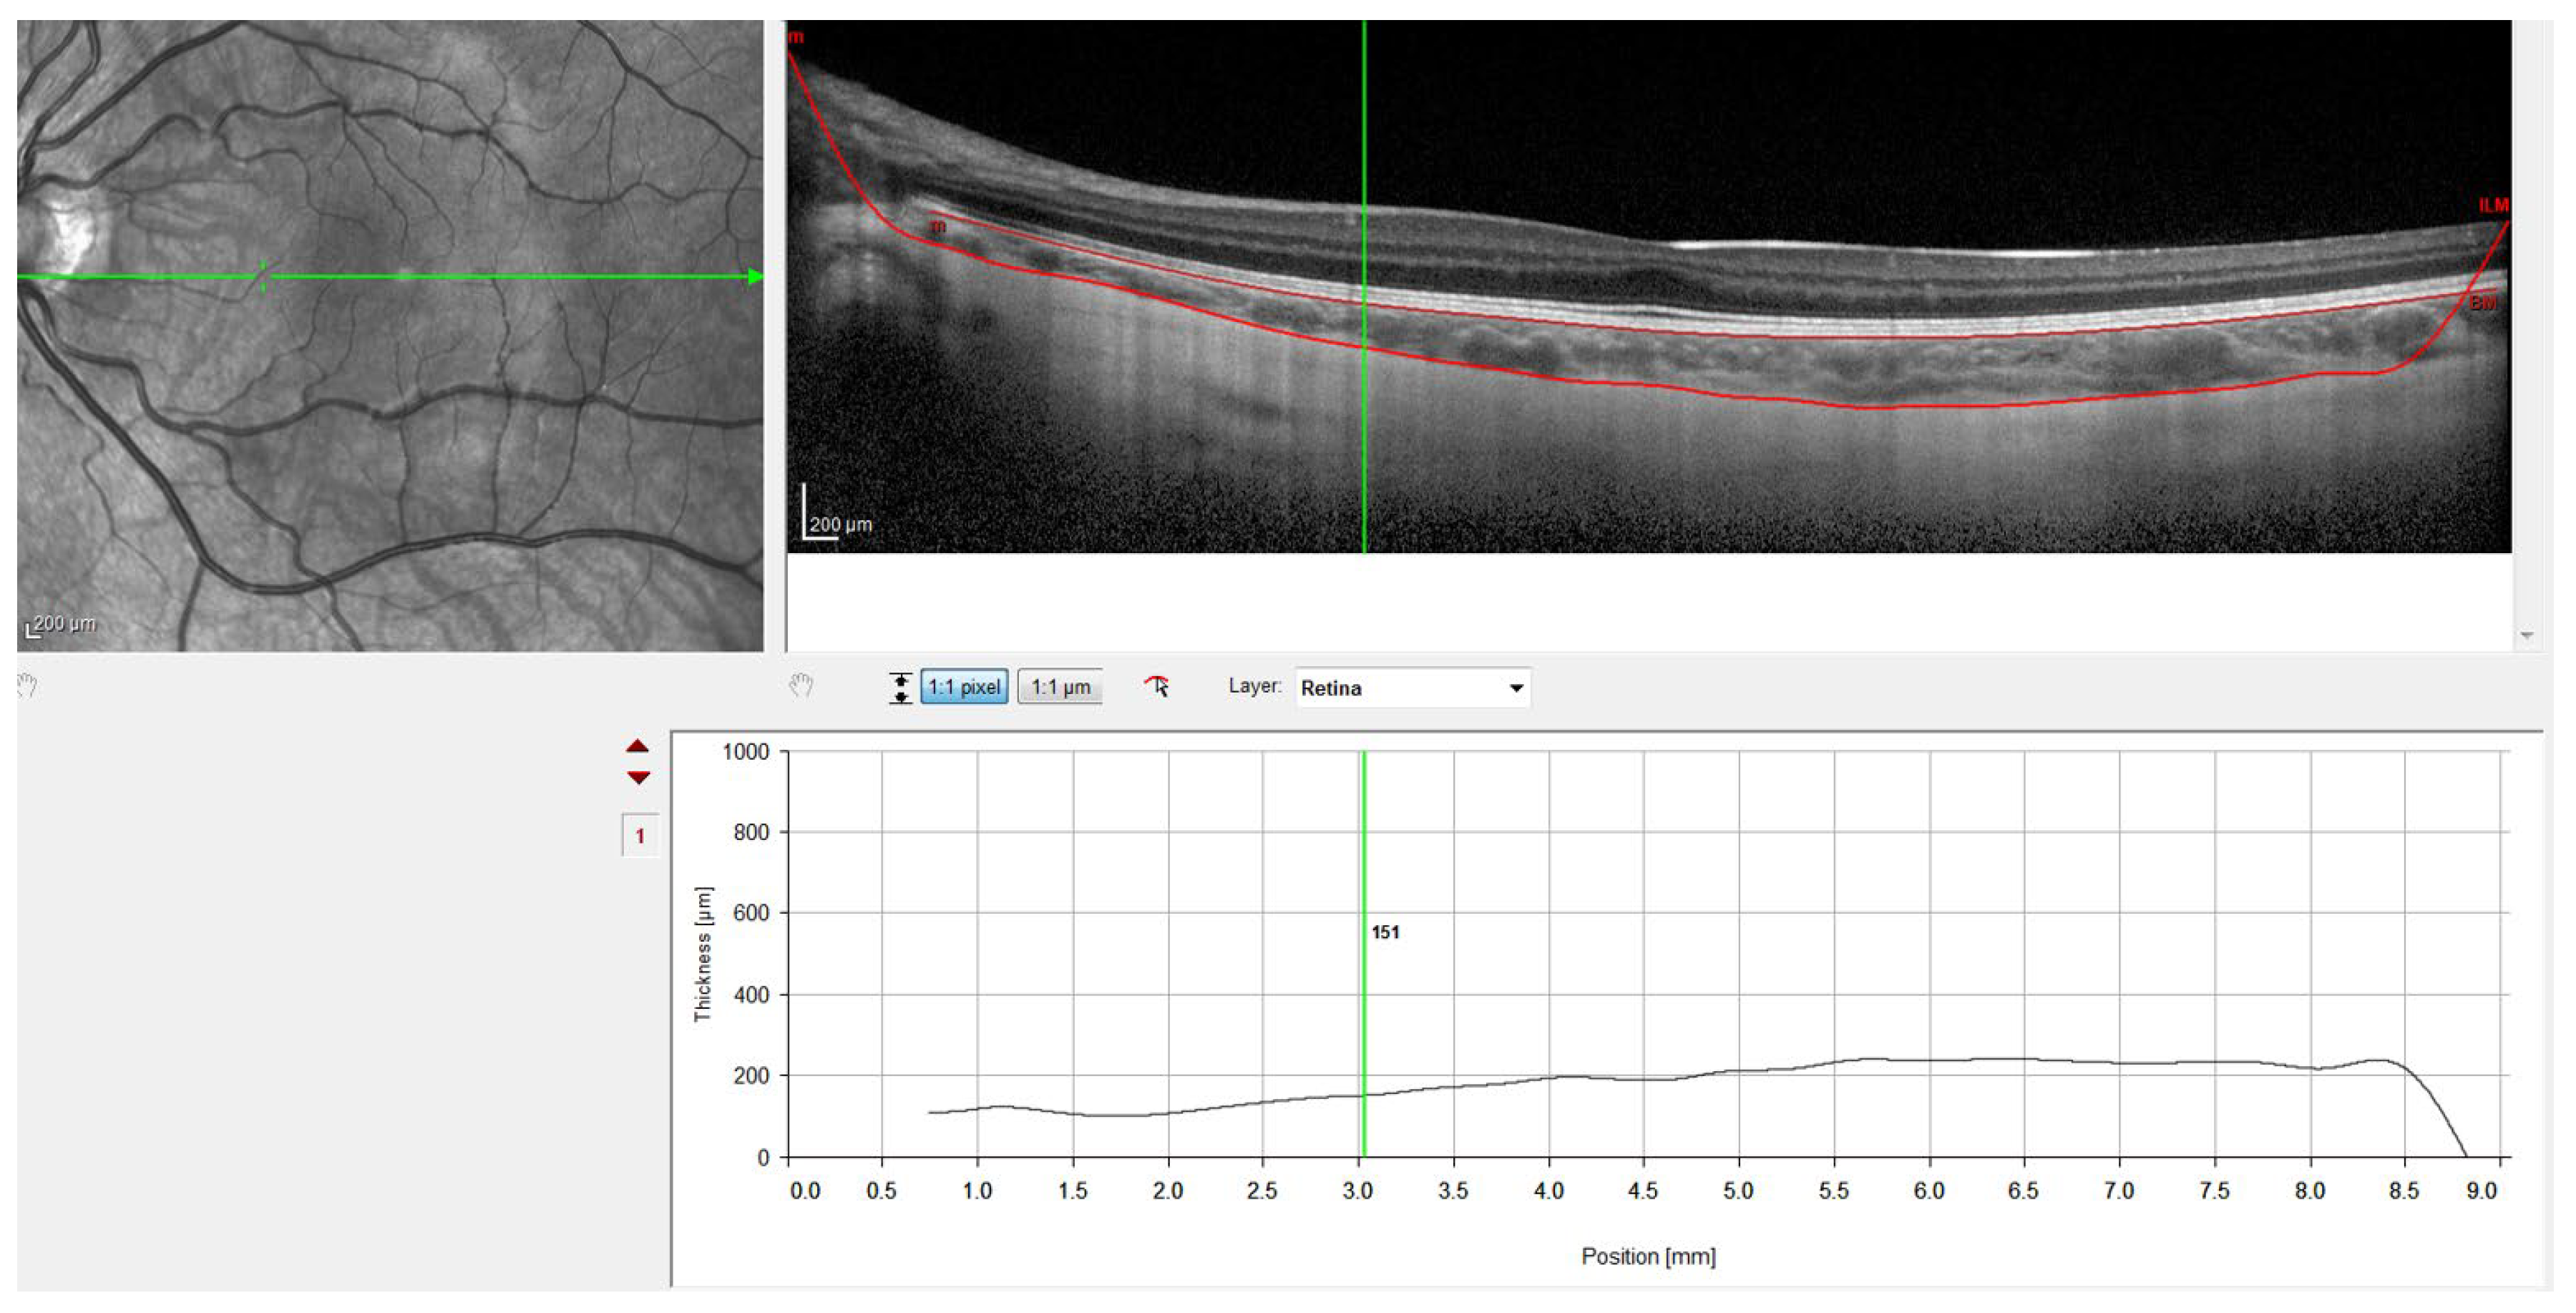

Figure 3.

OCT image with the sclero-choroidal interface marked in green, point by point.

Figure 4.

OCT image with lines in red corresponding to the retinal pigment epithelium and the sclero-choroidal interface.

Figure 2 shows when the internal limiting membrane was used to manually mark the division line between the choroid and sclera, moving that line point by point. Figure 3 shows the result of the movement of the line to define the sclero-choroidal interface.

Finally, Figure 4 shows the result with the retinal pigment epithelium layer, which was marked automatically by the software, and the division line between the choroid and sclera, which was marked manually. Figure 4 also shows how the gauge provided by the instrument was used to perform the measurements at the points defined in the study protocol. Therefore, to ensure that all measurements were taken at the same points, the measuring bar provided by the device was used to locate the center of the fovea and 1 and 3 mm nasal and temporal to the fovea. All the OCTs were conducted and analyzed by the same observer to ensure that they were taken from the same point as the first measurement.